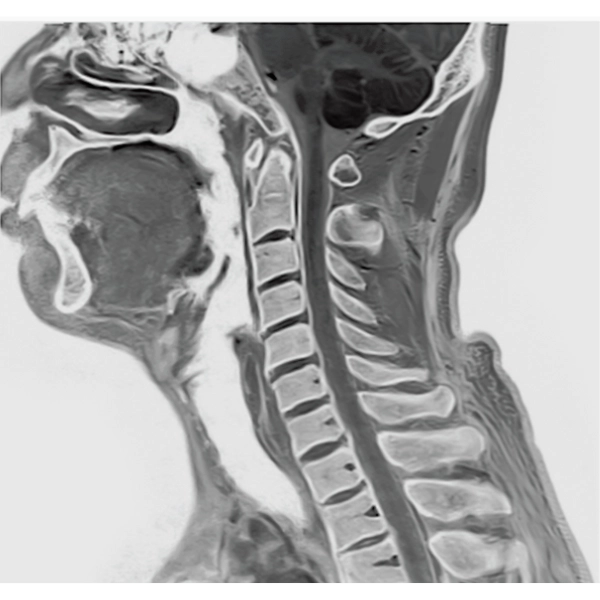

IP-RAPID x DLR Plus gives you the flexibility to shorten respiratory gated series or even replace them with breath-holds, depending on the patient’s situation. This gives you more options and a wider range of examinations to choose from.

IP-RAPID x DLR Plus can be used for basic imaging such as VolumeScan, RadialScan, HalfScan, and many other imaging methods such as MultiContrastScan FatSep and DWI.

It can also be used with time-consuming scans such as Whole Body DWI and Whole Spine imaging, providing more detailed information in many areas than previously possible.